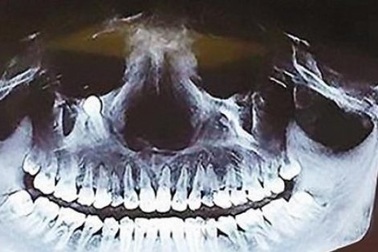

Hy hữu: Răng mọc ngầm chọc thủng hốc mũiNgười đàn ông đi khám vì đau nhức xương hàm trên đã lâu, chảy dịch mũi thường xuyên, bác sĩ phát hiện răng thừa ngầm trong xương hàm. Chiếc răng chọc thủng hốc mũi, phá huỷ xương hàm.

Răng mọc ngược lên mũiChiếc răng lẽ ra nằm ở hàm trên thì lại chen vào mũi khiến anh Lê Văn Vấn (39 tuổi, ở phường Hà Phong, thành phố Hạ Long, Quảng Ninh) bị khó thở, ù tai.

Hi hữu: Răng mọc trong mũi của bé gái 4 tuổiThay vì mọc trong miệng, chiếc răng của bé gái 4 tuổi (Hà Nội) lại mọc "lạc chỗ" ở trong mũi của bệnh nhi.

Mất khứu giác 3 năm, người đàn ông bàng hoàng phát hiện răng mọc trong… mũiLiên tục khó thở, mất khứu giác, thậm chí chảy máu cam liên tục, người đàn ông đi khám và phát hiện ra sự thật kinh hoàng: chiếc răng bị mọc "ngược” lên… mũi.